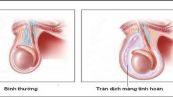

Tràn dịch màng tinh hoàn là tình trạng thường gặp ở trẻ sơ sinh và có thể tự khỏi. Tuy nhiên, bệnh cũng xuất hiện ở nam giới trưởng thành. Cùng eLib.VN tìm hiểu bài viết dưới đây để hiểu rõ hơn nhé!